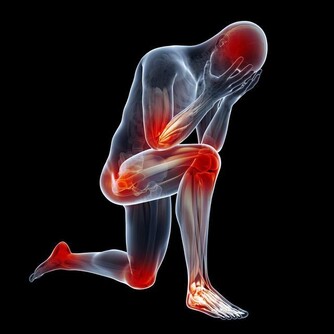

血管堵塞的症狀

1、 胸口悶痛

中老年人身上如果出現了胸口疼痛的現象,有可能是由於血管堵塞導致的。因為血管堵塞會導致人的身上出現心臟供血不足的現象,進而就會導致人的身上出現胸口疼痛的現象。

2、 四肢腫脹疼痛

四肢肢是人體供血的最末端,當血管堵塞後,四肢的供血和回血不足就會出現腫脹現象。四肢組織處於缺血缺氧狀態下就會伴隨有疼痛的表現,特別是靜脈血栓發生後,腫脹症狀更為明顯。